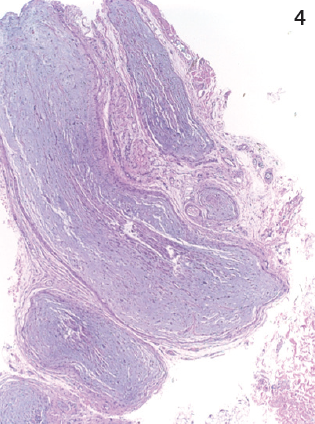

Later, when the girl was 10 months old, a biopsy specimen of the skin of her left palm showed neurofibroma; a biopsy specimen of a brown plaque on her back showed plexiform neurofibroma (Figure 3). Magnetic resonance imaging (MRI) scans, with and without contrast, of her chest and abdomen showed multiple infiltrative masses in the neck, chest, and upper extremities, which initially were read as being consistent with venous malformations; later, in conjunction with other studies, these were reinterpreted as being consistent with internal neurofibromas (Figure 4). The girl received a diagnosis of neurofibromatosis type 1 (NF1). She was referred to the multidisciplinary Comprehensive Neurofibromatosis Clinic at Children’s Medical Center of Dallas.